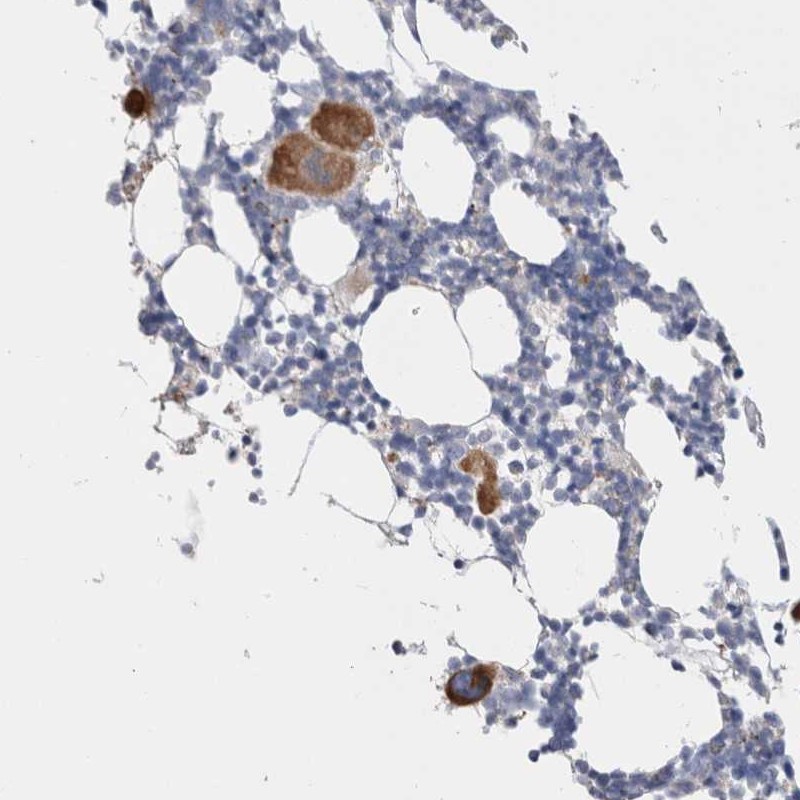

Immunohistochemical staining of human bone marrow shows strong cytoplasmic positivity in megakaryocytes.